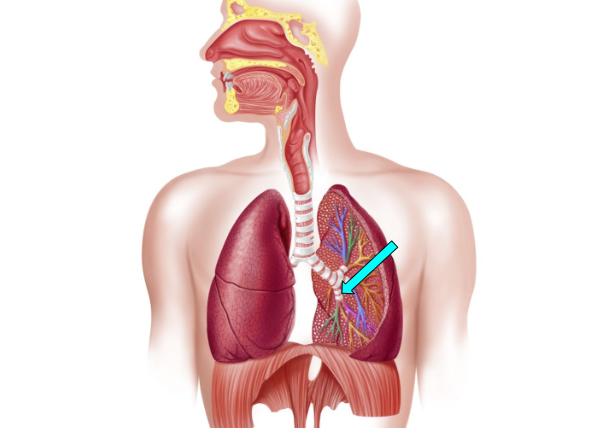

Bronchioles

small airway that delivers oxygen to the alveoli for gas exchange

Bronchi

carry oxygen to and from the lungs

Alveoli

facilitate gas exchange through the lungs & bloods to exchange oxygen & carbon dioxide during respiration

Bronchus (pic)

Bronchioles (pic)

Alveoli (pic)